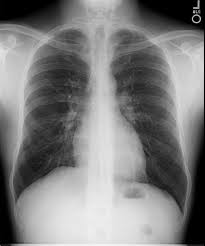

هذه صورة واحدة ربما تعلمون جميعا ما هي بمجرد رؤيتها، إنها صورة مألوفة المظهر، شيء ربما نحن جميعًا لدينا بعض الخبرة الشخصية معها، أليس كذلك؟

هذه صورة للصدر بالأشعة السينية التي قد تؤخذ في عيادة الطبيب على سبيل المثال، أو في عيادة طبيب الأشعة. تُعد مثالًا جيدًا للهندسة الطبية الحيوية، تأخذ مبدأ فيزيائيًا، وهو كيف تتفاعل الأشعة السينية مع أنسجة الجسم، وتستخدم مبادئ الفيزياء، وهذا المبدأ المادي لوضع صورة لما يدور في داخل جسمك، وذلك للنظر في الداخل ورؤية الأشياء التي لا يمكن أن تُرى من دون هذا الجهاز، وسوف تتعرف على بعض أجزاء الصورة. تستطيع أن ترى القفص الصدري، العظام، تستطيع أن ترى القلب، هذا الكائن الكبير ذو اللون الفاتح في الأسفل. إذا كان لديكم بصر جيد فقد ترون الأوعية الخارجة من القلب وإلى الرئتين، هذه المساحات المظلمة داخل القفص الصدري.

تعلّم الأطباء على مر السنين من خلال وجود هذا الجهاز كيف يُكوّنون نظرةً متطورة للغاية من خلال هذه الصور والتشخيص الدقيق عندما يكون هناك شيء خاطئ داخل الصدر على سبيل المثال، لذلك هذا هو مثال للهندسة الطبية الحيوية، مثال مندمج بشكل جيد في مجتمعنا لدرجة أنه لربما حصلنا جميعنا على صورة مشابهة سابقًا.